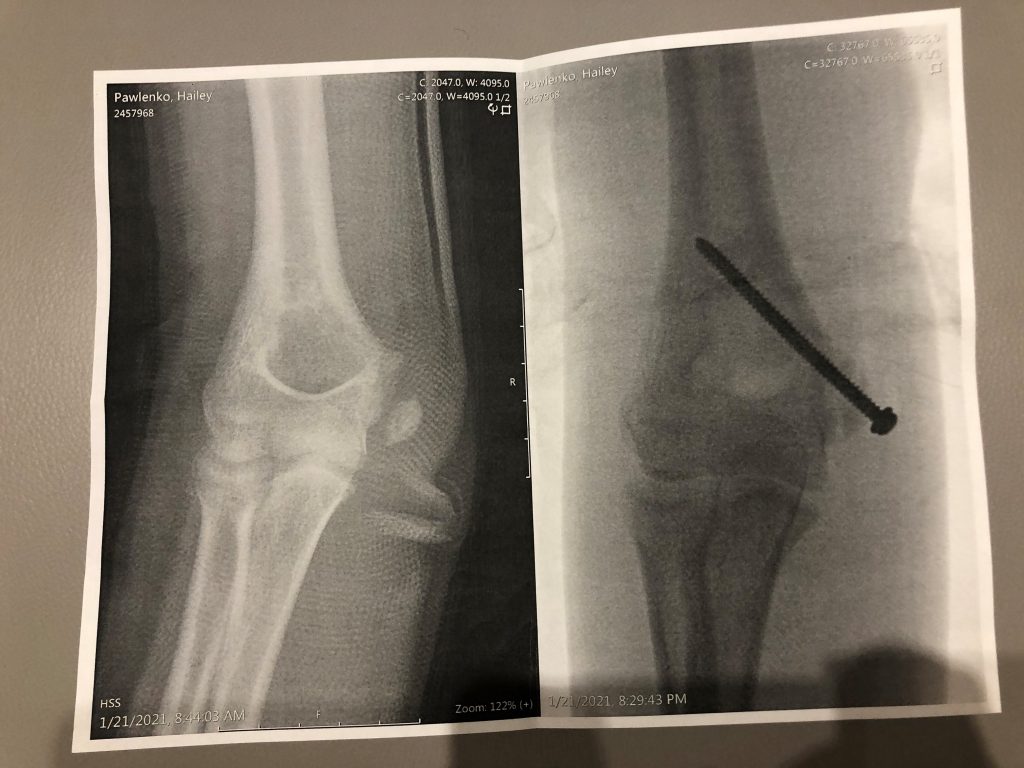

Hello all. I wanted to take a moment to introduce you to Hailey. Hailey is a level 8 competitive gymnast, that was training level 9. In the world of gymnastics, there are only 10 levels. Hailey was on top of the world, with many accomplishments in the sport of gymnastics. She had to suffer through gyms being shut down due to COVID, and was finally getting back to training. Unfortunately, during a virtual meet, she had a devastating elbow injury with a displaced avulsion fracture of medial epicondyle left humerus. In other words, she broke her elbow and would require surgery.

We took her for an x-ray locally and were told she may need emergency surgery that day. Having had experience with Dr. Fabricant (who treated my son for an ankle injury) and HSS, we called over to see if they could get us in for an emergency appointment. The next day she went to HSS and that night, Dr. Fabricant performed surgery on her, which she had a big screw in her elbow as a result. Hailey’s injury is somewhat controversial in that some doctors choose to just cast the elbow. Having had no prior experience with surgery, the nerves kicked in. I didn’t want just anyone to treat my daughter, I wanted the best of the best and I wanted reassurance that Hailey was being treated the right way from the start. HSS did just that. From the check in at the reception to the x-rays and the recovery, everyone was top notch. I honestly never second guessed my decision. We even had a million dollar view of New York City!